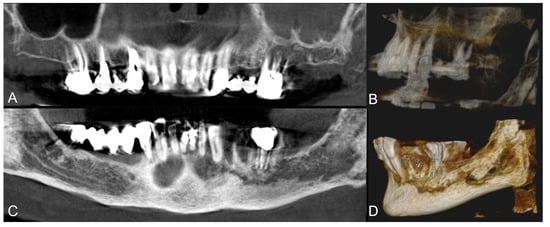

Group A showed higher complete healing cases when compared to group B (Figure 1, Figure 2, Figure 3 and Figure 4).

Figure 4. Group B patient. Radiological pre-operative assessment through cone beam computed tomography of a stage 2 maxillary and mandibular MRONJ. Axial view (A) and mandibular view (B). Twelve months follow-up axial view (C).